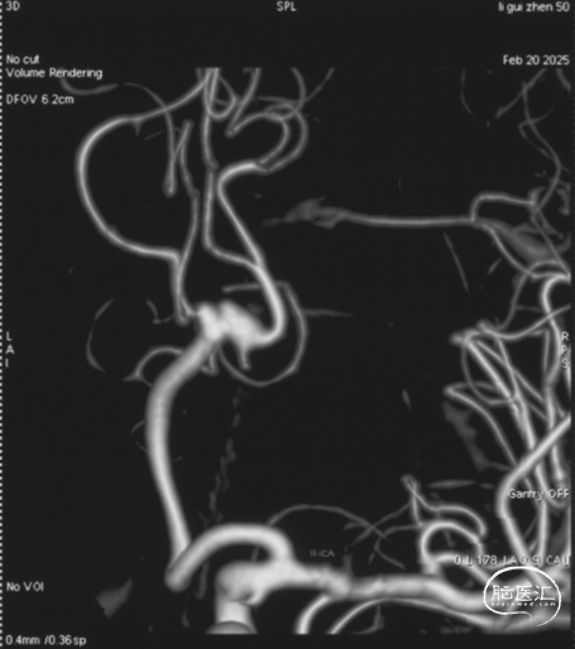

右侧颈内正位造影

右侧颈内侧位造影

载瘤动脉远端血管直径:2.1mm

载瘤动脉近端血管直径:1.8mm

动脉瘤尺寸:瘤颈4.69mm,大小3.25mm*4.21mm*4.24mm;指向右上

近端狭窄:最窄处:0.53mm,远心端2.1mm,近心端2.2mm,长度11.23mm